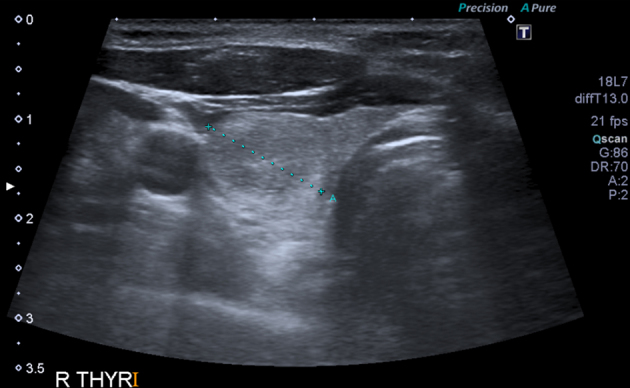

The patient underwent ultrasonography guided biopsy of the right neck because of the proximity of the lymph node to the neck vessels. The ultrasonography (Fig 1) showed a 1.3cm lesion with acoustic shadowing giving the impression of possible calcinosis but the nature of the lesion could not be discerned fully. Fine needle aspiration was equally inconclusive, showing multinucleated giant cells with foamy cytoplasm, and it could not rule out malignancy. The patient then underwent computed tomography (CT) of the neck and chest (Fig 2), which revealed an enlarged supraclavicular node that looked benign. Bilateral breast implants were also noted.

Figure 1.

Ultrasonography showing 1.3cm lymph node with acoustic shadowing